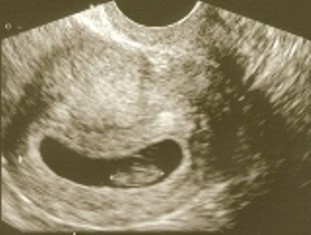

Dziewczyny, byłam wczoraj u mojej ginki i widziałam moje maleństwo, i nawet widziałam jak serduszko bije mojej fasolce. Bardzo miłe uczucie. Moje maleństwo ma 7 tygodni 3 dni i mierzy 10mm , przypuszczalna data porodu to 31.12.2011, ale nic nie wiadomo bo miałam nieregularne miesiączki(a data porodu szacowana przez USG). Następna wizyta 20 czerwca, ponieważ bedzie wtedy 12 tydz.

Moja malutka fasoleczka:-)